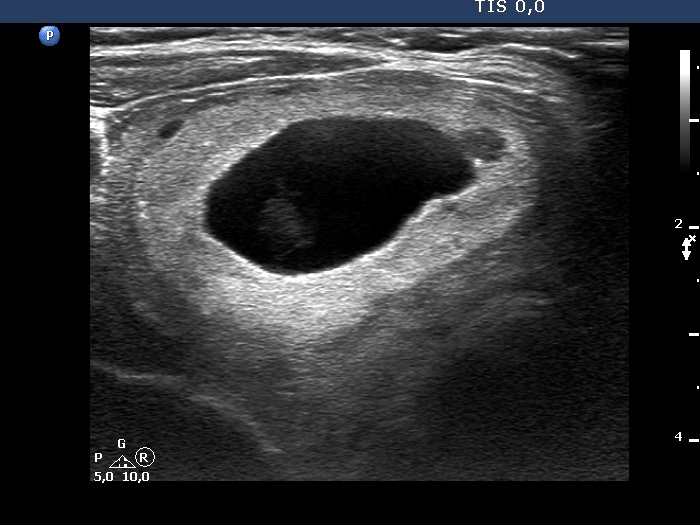

TIRADS - case 1530

Examination 3 years later (ultrasonographic picture 2)

Right lobe, longitudinal scan.